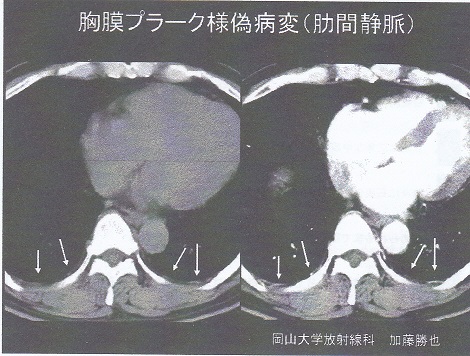

石綿による胸膜プラークと鑑別が必要な病態としては以下のものがある。

① 結核性胸膜炎後の石灰化病変

② 肺尖肥厚

③ 胸膜下脂肪層

④ 肋間静脈

⑤ 胸膜直下肺野病変

https://www.rofuku.go.jp/Portals/0/data0/sanpo/kadai/pdf_slide/h18/h18slide_hyogo.pdf

⑥ 胸横筋 第Ⅱ~Ⅳ肋軟骨路胸骨下を結ぶ筋

胸膜プラークの検出率は、単純レントゲンでは35%程度であること、CTも撮影条件によっては1/3程度描出できない点注意が必要である。